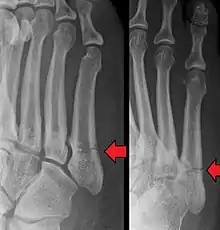

A person with a Jones fracture may not realize that a fracture has occurred. Diagnosis includes the palpation of an intact fibularis brevis tendon, and demonstration of local tenderness distal to the tuberosity of the fifth metatarsal, and localized over the shaft of the proximal metatarsal.

Diagnostic X-rays include anteroposterior, oblique, and lateral views and should be made with the foot in full flexion.

- Proximal diaphysis, typically stress fracture.[12][13]

- Metaphysis: Jones fracture[14]

-Tuberosity: Pseudo-Jones fracture[15] (avulsion fracture).[15]

Other proximal fifth metatarsal fractures exist, although they are not as problematic as a Jones fracture. If the fracture enters the intermetatarsal joint, it is a Jones fracture. If, however, it enters the tarsometatarsal joint, then it is likely an avulsion fracture caused by pull from the fibularis brevis tendon. An avulsion fracture at the base of the fifth metatarsal is sometimes called a "dancer's fracture" or a "pseudo Jones fracture", and usually responds readily to non-operative treatment.[18] The X-ray appearance of the developmental "apophysis" in this area may have some resemblance of a fracture, but is not a fracture; it is the secondary ossification center of the metatarsal bone. It is a normal finding that occurs at this site in adolescents.[19] If an injury to that area has occurred, the physician is often able to interpret certain radiographic clues to make the differentiation. An avulsion fracture at this location is typically extra-articular and oriented transversally as compared to the longitudinal orientation of an unfused apophysis.[19]